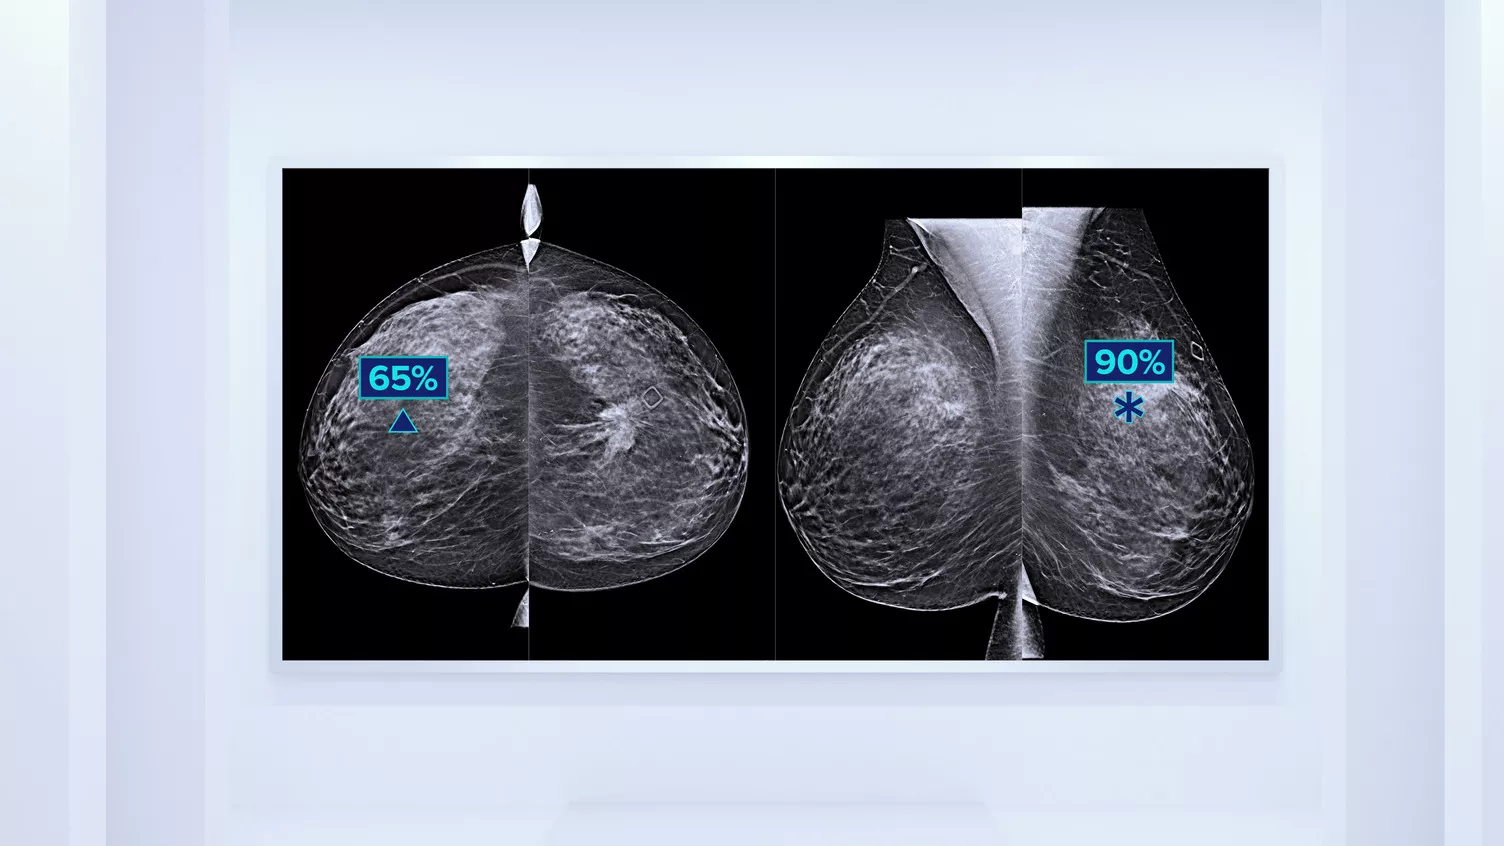

Higher breast density is known to increase a woman’s risk for breast cancer.1 The need for accurate, unbiased analysis is therefore critical. Powered by machine learning, Quantra technology software analyses both 2D™ and tomosynthesis images for distribution and texture of parenchymal tissue. It categorizes breasts in four breast composition categories consistent with guidance from the American College of Radiology (ACR) BI-RADS Atlas 5th Edition.2

In addition to volume, pattern and texture of fibroglandular tissue may play just as an important role in mammographic cancer risk prediction.3-5 By analyzing and categorizing breast texture and pattern, our technology can deliver the accurate information you need to achieve more consistent and reliable scoring and confidently design patient-specific screening.

Objective machine learning algorithm that assigns breast density category based on analysis of breast tissue texture and patterns.

Quantra software’s unbiased algorithm analyse both 2D and tomosynthesis images to support your analysis by:

- Overcoming subjectivity in visual assessment, providing more consistent, and more reliable scoring.*